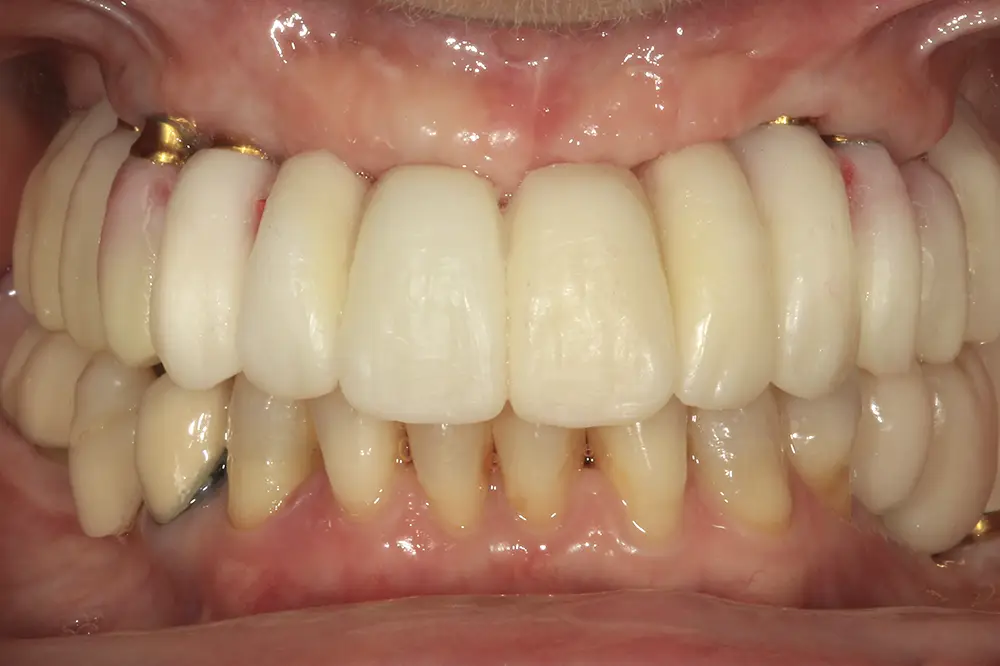

Para los sectores posteriores, se fabricaron estructuras mediante fresado CAD/CAM del mismo modo que la barra anteriormente descrita, con la diferencia de que sobre ellas se colocó un recubrimiento de cerámica (figs. 47-49). La paciente continúa en seguimiento, sin evidenciarse pérdidas óseas significativas en ninguno de los implantes estrechos y cortos que conforman la restauración de todo el maxilar superior tras tres años de carga de la prótesis definitiva (y hasta 4,5 de la carga de los implantes de la fase inicial de carga inmediata) (fig. 50).

Figs. 47 y 48. Prótesis terminadas, colocadas en la paciente.